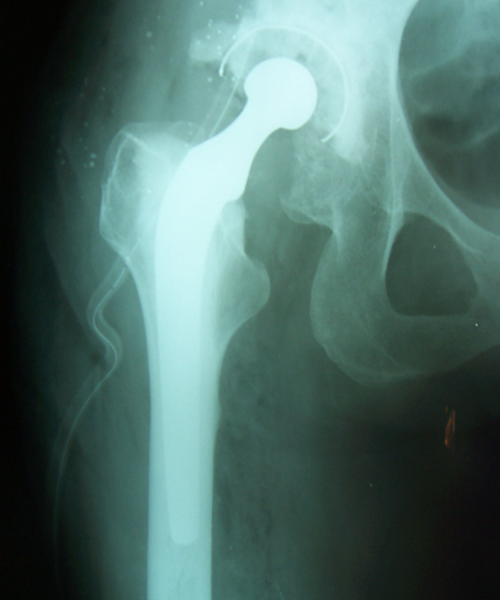

Case:4 Post Tuberculous Ankylosed Hip

Arthroscopy Surgeon in Ahmedabad|Best Trauma Surgeon in Ahmedbad

Pre-op

Arthroscopy Surgeon in Ahmedabad|Orthopedic Oncology Doctor

Post-op